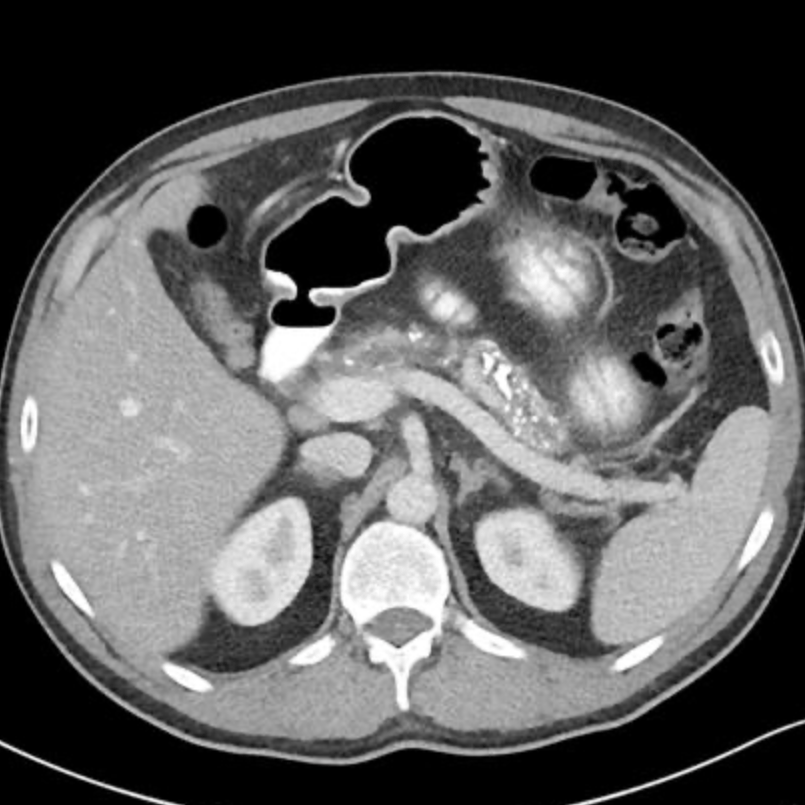

통상적인 복부CT의 횡단면영상입니다. 대부분의 경우 췌장의 머리부위에서 꼬리부위까지 하나의 단면으로 모두 볼 수 있는 영상은 현실에서는 좀처럼 찾아보기 어렵습니다. 원래 췌장이라는 장기는 튜브처럼 일직선으로 빳빳하게 펴져있는 장기가 아니라, 마치 두부처럼 부들부들해서 주변 장기에 눌려 비틀려있기 때문에 하나의 단면으로 전장을 확인할 수 없는 경우가 대부분입니다.

특히나, 비장정맥은 췌장의 절반정도만을 함께 주행하는 경우가 대부분입니다. 췌장의 뒤쪽을 가로지르며 주행하는 비장정맥은 초음파영상에서 췌장을 구분하게 해주는 랜드마크로 알려져 있지만, 대부분 췌장의 목 부위에서 몸통의 일부분까지만 췌장과 함께 주행하면서 췌장의 뒷쪽 경계를 형성하는 경우가 대부분입니다. 위의 CT영상에서도 확인할 수 있듯이 비장정맥을 따라가다 보면 잘해봐야 췌장의 몸통부분까지만을 확인할 수 있는게 정상입니다.